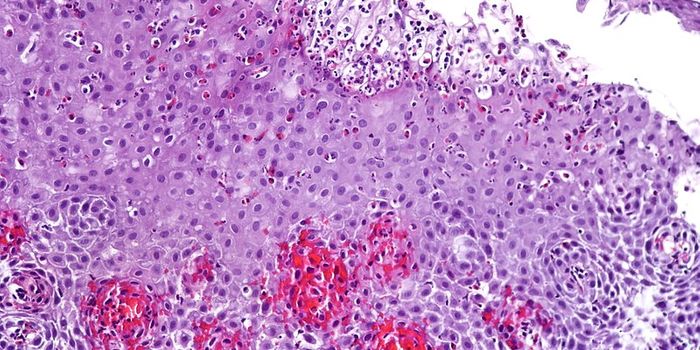

Follow a curation of discoveries and updates in immunology focusing on immune responses to infectious disease, structure and function, and developments in the defense against infection.